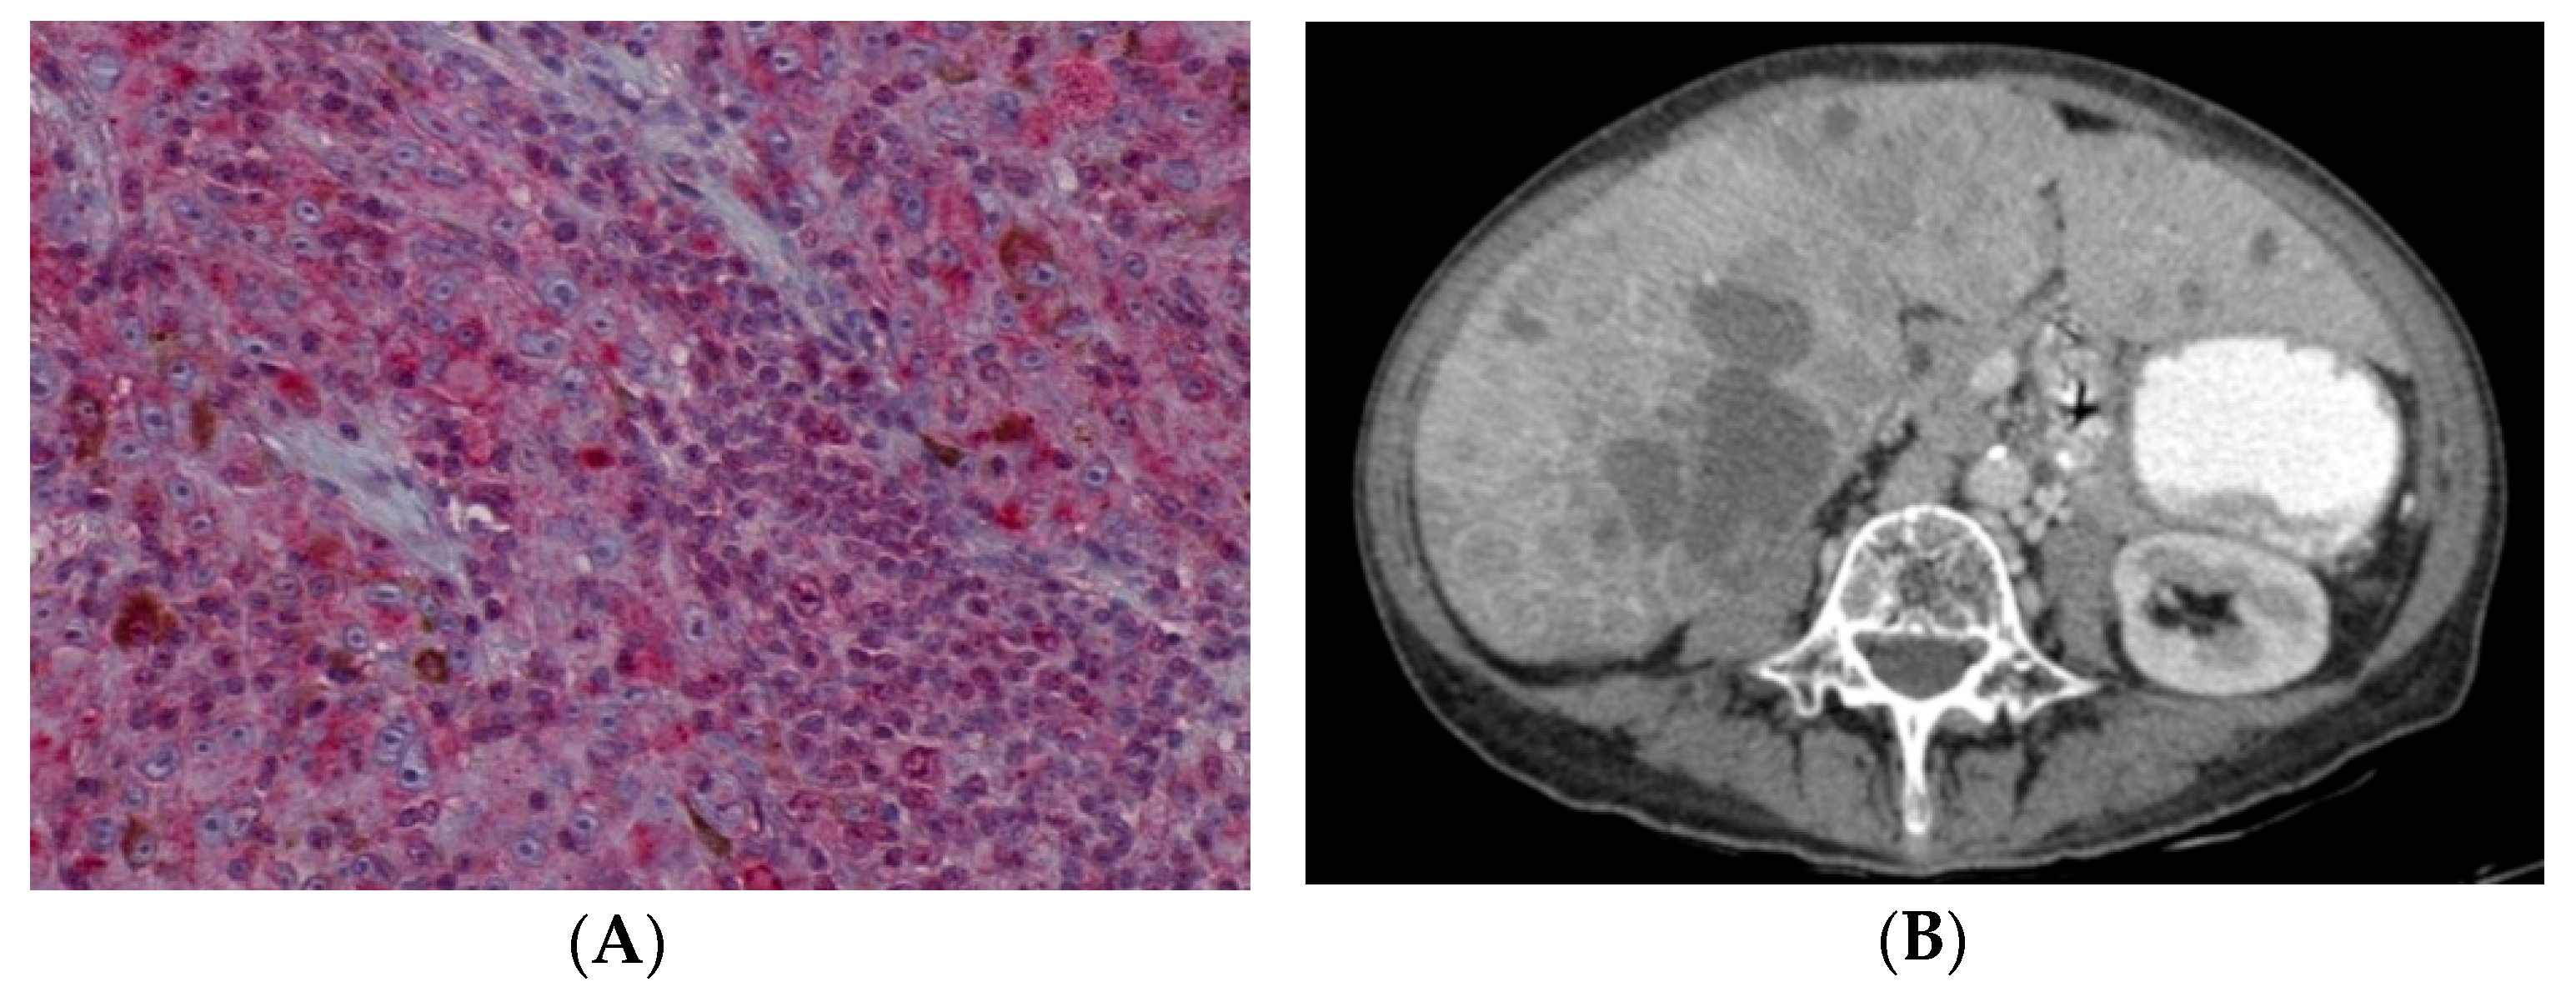

The most intense BAP1 stained areas were selected for grading under 40× magnification. The samples with nuclear (Figure 2A–D) and cytoplasmic staining were separated from each other (Figure 3A–D) using the following scoring system: 0 = positive staining in less than 10% of cells per high-power field, 1 = positive staining in between 10% and 33% of cells per high-power field, 2 = positive staining in between 34% and 66% of cells per high-power field, and 3 = positive staining in ≥66% of cells per high-power field. Positive BAP1 immunoreactivity was shown by an increase in red staining in the cellular nucleus or cytoplasm (Figure 2D and Figure 3D); while negative BAP1 immunoreactivity was shown by a decrease in red staining which caused the cells to have a blue appearance (Figure 2A and Figure 3A). The retinal pigment epithelium and the lymphocytes were used as positive controls for BAP1 expression (Figure 2A white arrows).

H&E image (Figure 4A) and grade 0 of BAP1 nuclear staining with grade 3 of BAP1 cytoplasmic staining image (Figure 4B) in the same sample of UM are shown.

Figure 4.

Uveal melanoma sample. (A) H&E image (×200). (B) Grade 0 of nuclear BAP1 staining with grade 3 of cytoplasmic BAP1 staining (×200).

Metastatic rates were different between patients with low grade and high grade nuclear BAP1 stain (p < 0.001). Low grade stain was recorded in sixteen metastatic UM patients (88.9%) and in seven non-metastatic UM patients (36.8%). By contrast, only two patients with a high grade nuclear BAP1 stain showed metastasis (14.3%). This was comparable with other studies in which lower nuclear immunoreactivity was observed in patients with a high risk of metastatic UM [1,8,15,19,25,40]. Moreover, death due to metastasis was greater among patients with lower nuclear BAP1 stain (92.9%) (Figure 7A,B) than in patients with higher nuclear BAP1 stain (20%). The liver was the most affected organ in both grades (65.2% in lower grade and 7.1% in higher grade). Furthermore, survival analysis demonstrated a significant association between low grade staining and reduced survival time.

Figure 7.

(A) H&E image (×200): Low grade nuclear BAP1 staining in a patient who died due to uveal melanoma metastasis. (B) Liver metastasis in an axial slice of a computed tomography scan.